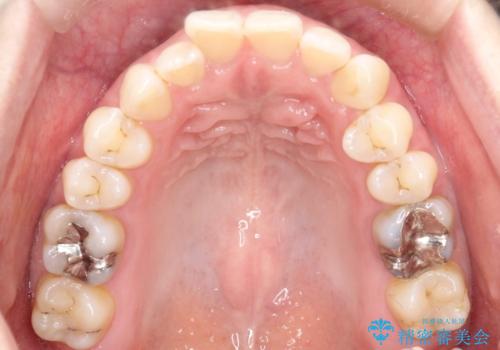

- 右上の前から2番目と3番目の歯が内側に引っ込んでしまっているのを主訴に来院されました。

右上の2番目と3番目のはが前後反対にかんでしまっている状態でした。

インビザラインにて治療することとしました。

内側に引っ込んでいる歯も、インビザラインにてしっかり外側に動かすことができます。